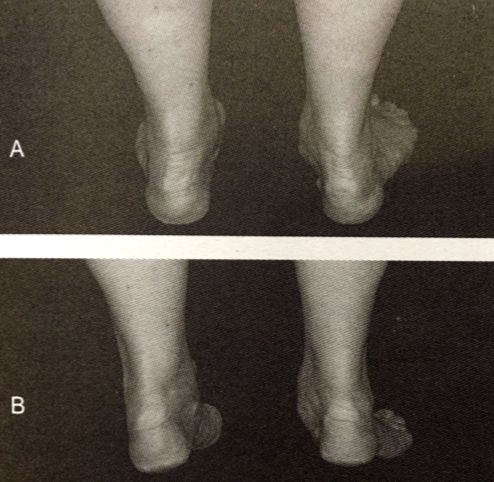

单腿趾尖试验。该患者在右侧有胫骨后裂开;A.站立时足跟处于外翻位;B.当足尖足趾与足跟在外翻位时,该患者无法进行单腿趾尖测试。